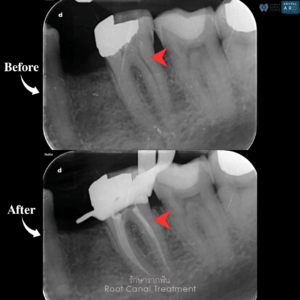

รักษารากฟัน

คือ การรักษาฟันที่เกิดการอักเสบและติดเชื้อภายในโพรงประสาทฟัน และเนื้อเยื่อรอบปลายรากฟัน อันมีสาเหตุมาการอักเสบและติดเชื้อภายในรากฟัน โดยทันตแพทย์จะทำการทำความสะอาดและใส่ยาในคลองรากฟัน และทำการอุดรากฟันเป็นขั้นตอนสุดท้าย การรักษารากฟันจะช่วยเก็บรักษาฟันให้สามารถคงอยู่ในช่องปากต่อได้ โดยไม่ต้องถอนฟันและไม่ต้องใส่ฟันทดแทน